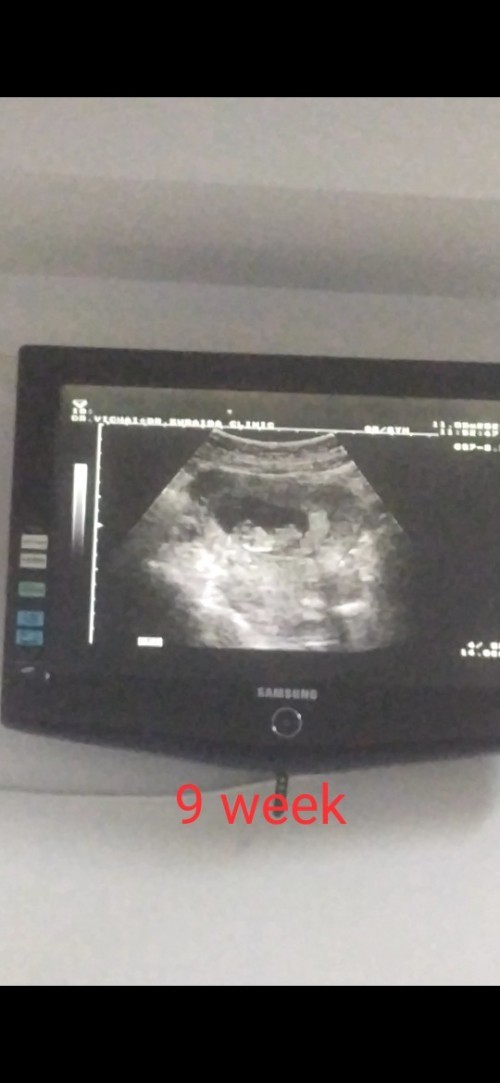

10วีคค่า👶🏻🤍👋🏻